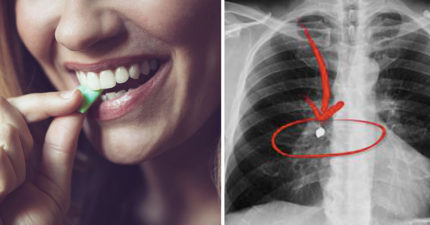

口香糖吞下肚會怎樣?「食物全黏成一團」把腸子都塞住!

July 12, 2018

世界